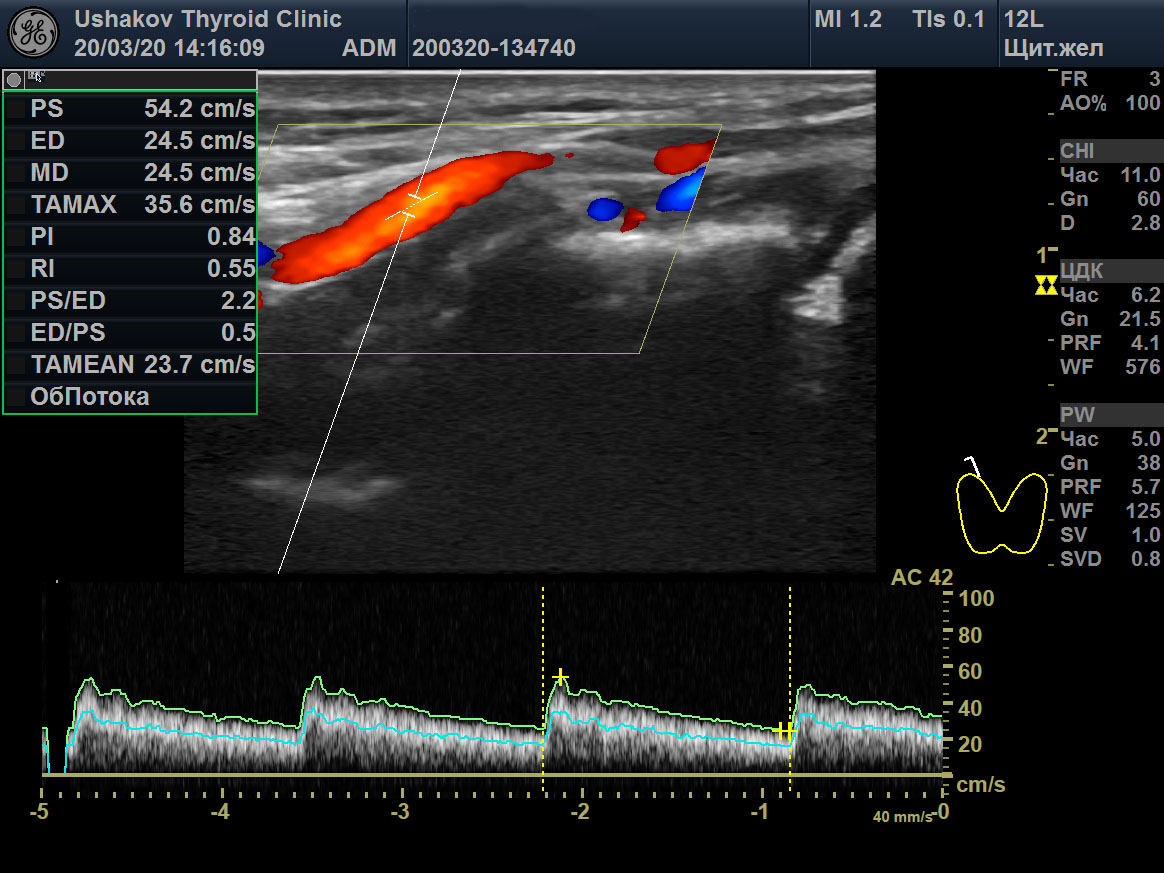

Пример такого случая представлен на

снимках ниже, где показаны две доли ЩЖ пациентки 31 года в режиме ЭДК и ПССК в системе верхних щитовидных артерий (ВЩА). Интенсивность кровотока при ЭДК усилена до значительной степени, а ПССК – до умеренно избыточной величины (норма 20-30 см/с [127]).

Рисунок 1 Левая и правая доли ЩЖ пациентки 31 года (поперечные и продольные проекции в режиме ЭДК; ПССК в режиме ЦДК), УЗИ 20.03.2020. Объём ЩЖ 9,1 мл (рост 170 см, масса 50 кг). Данные анализа крови от 18.03.2020: ТТГ 33,6 мЕд/л [0,4-4,0], Т4св. 6,7 пмоль/л [9,0-19,0], Т3св. 4,1 пмоль/л [3,0-5,6], АТТПО >1000 Ед/мл [<5,6], АТ-ТГ 368,8 Ед/мл [<18]. ПССК в системе ВЩА слева и справа 54 см/с. Концентрация йода в моче 200 мкг/л. Медикаменты не принимает продолжительный период.

В результате при обращении в нашу Клинику были выявлены признаки значительного перенапряжения ЩЖ по данным УЗИ в виде значительной интенсификации тиреоидного кровотока (

рис. 1). Эта избыточная стимуляция ЩЖ со стороны гипофиза (ТТГ 33,6 мЕд/) и периферической ВНС, тем не менее, сопровождалась

адекватным отношением увеличенных скоростей выделения (щитовидной железой) и потребления (организмом) гормонов,

поддерживающим уровень главного потребляемого гормона Т3св. в оптимальной концентрации в крови (т.е. в середине нормы: 4,1 пмоль/л [3,0-5,6]). В том числе поэтому, несмотря на то что такие значения гормональных показателей называют «манифестным гипотиреозом», пациентка не жаловалась на ухудшение самочувствия.